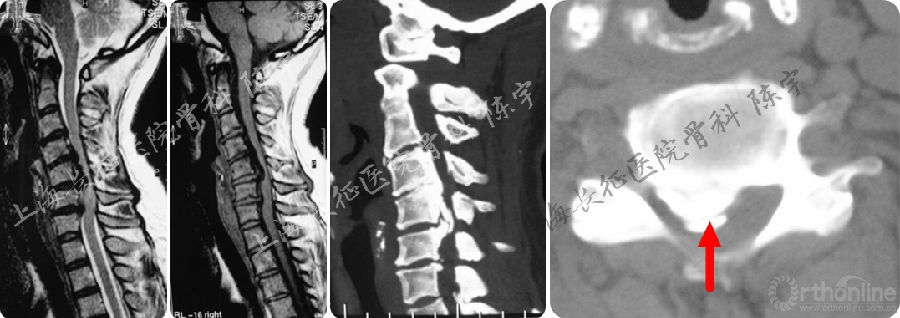

术后影像学检查(图2):

(1) X线:显示颈前路C4-6椎体次全切除减压钛网植骨融合术;

(2) MRI:显示术后脊髓减压充分,脊髓形态完全恢复;

(3) CT: 显示后纵韧带骨化物完全切除,硬膜囊骨化保留并向前漂移。